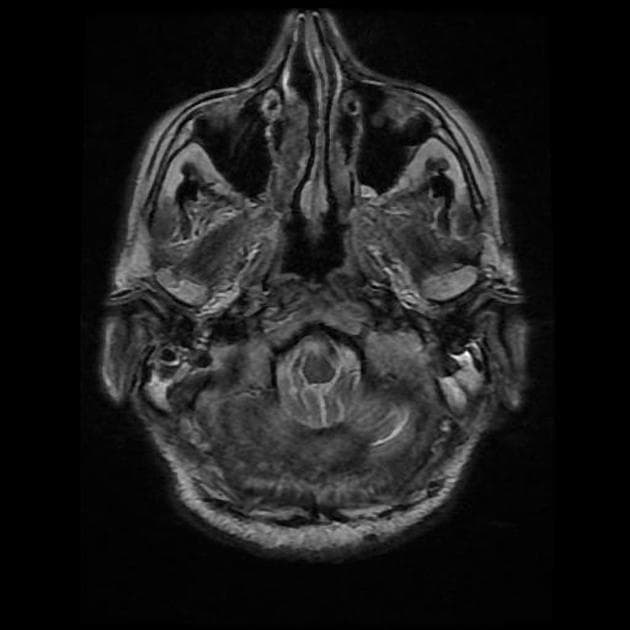

MRI

MRI nhạy hơn CT. Mặc dù các tổn thương viền ngấm thuốc có thể không đặc hiệu trên hình ảnh, nhưng các dãy hình khuếch tán (ít phổ biến hơn là phổ cộng hưởng từ – MR spectroscopy) cho thấy hạn chế khuếch tán ở trung tâm là yếu tố then chốt gợi ý chẩn đoán áp xe não.

-

T1

trung tâm giảm tín hiệu (tăng tín hiệu so với dịch não tủy)

vùng ngoại vi giảm tín hiệu (phù vận mạch)

ngấm thuốc dạng viền

viêm màng não thất có thể hiện diện, trong trường hợp này giãn não thất cũng thường được thấy